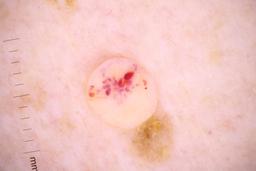

- Name: Challenge 2020: Training

- Number of images: 33,126

- Number of specified lesions: 32,701

- Number of specified patients: 2,056